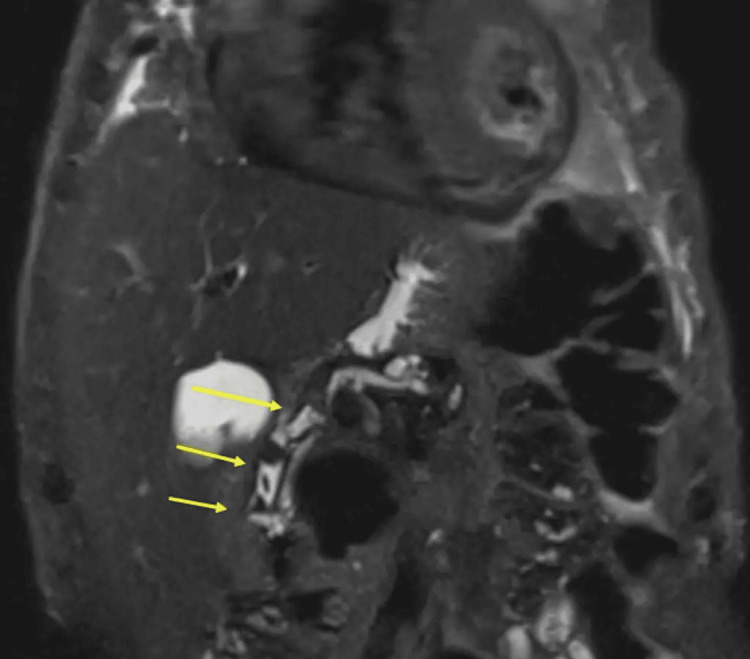

Thereafter, an in-patient magnetic resonance cholangiopancreatography (MRCP) was requested that showed three CBD calculi with a normal calibre biliary tree and sludge within the gallbladder (Figure 2).